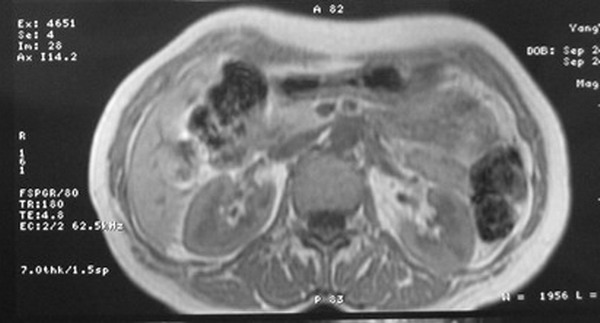

标题: MRI2066:腹膜后占位,请会诊,CT18531近期扫描图像

无明显不适,体检发现,

mri基本排除血管类肿瘤,明显强化说明极富血供,临床无症状,考虑胰岛细胞瘤可能大。

强化明显,并见有血管与之相连;考虑巨淋巴增生症.

极富血供的占位性病变,首先考虑良性,期待结果。